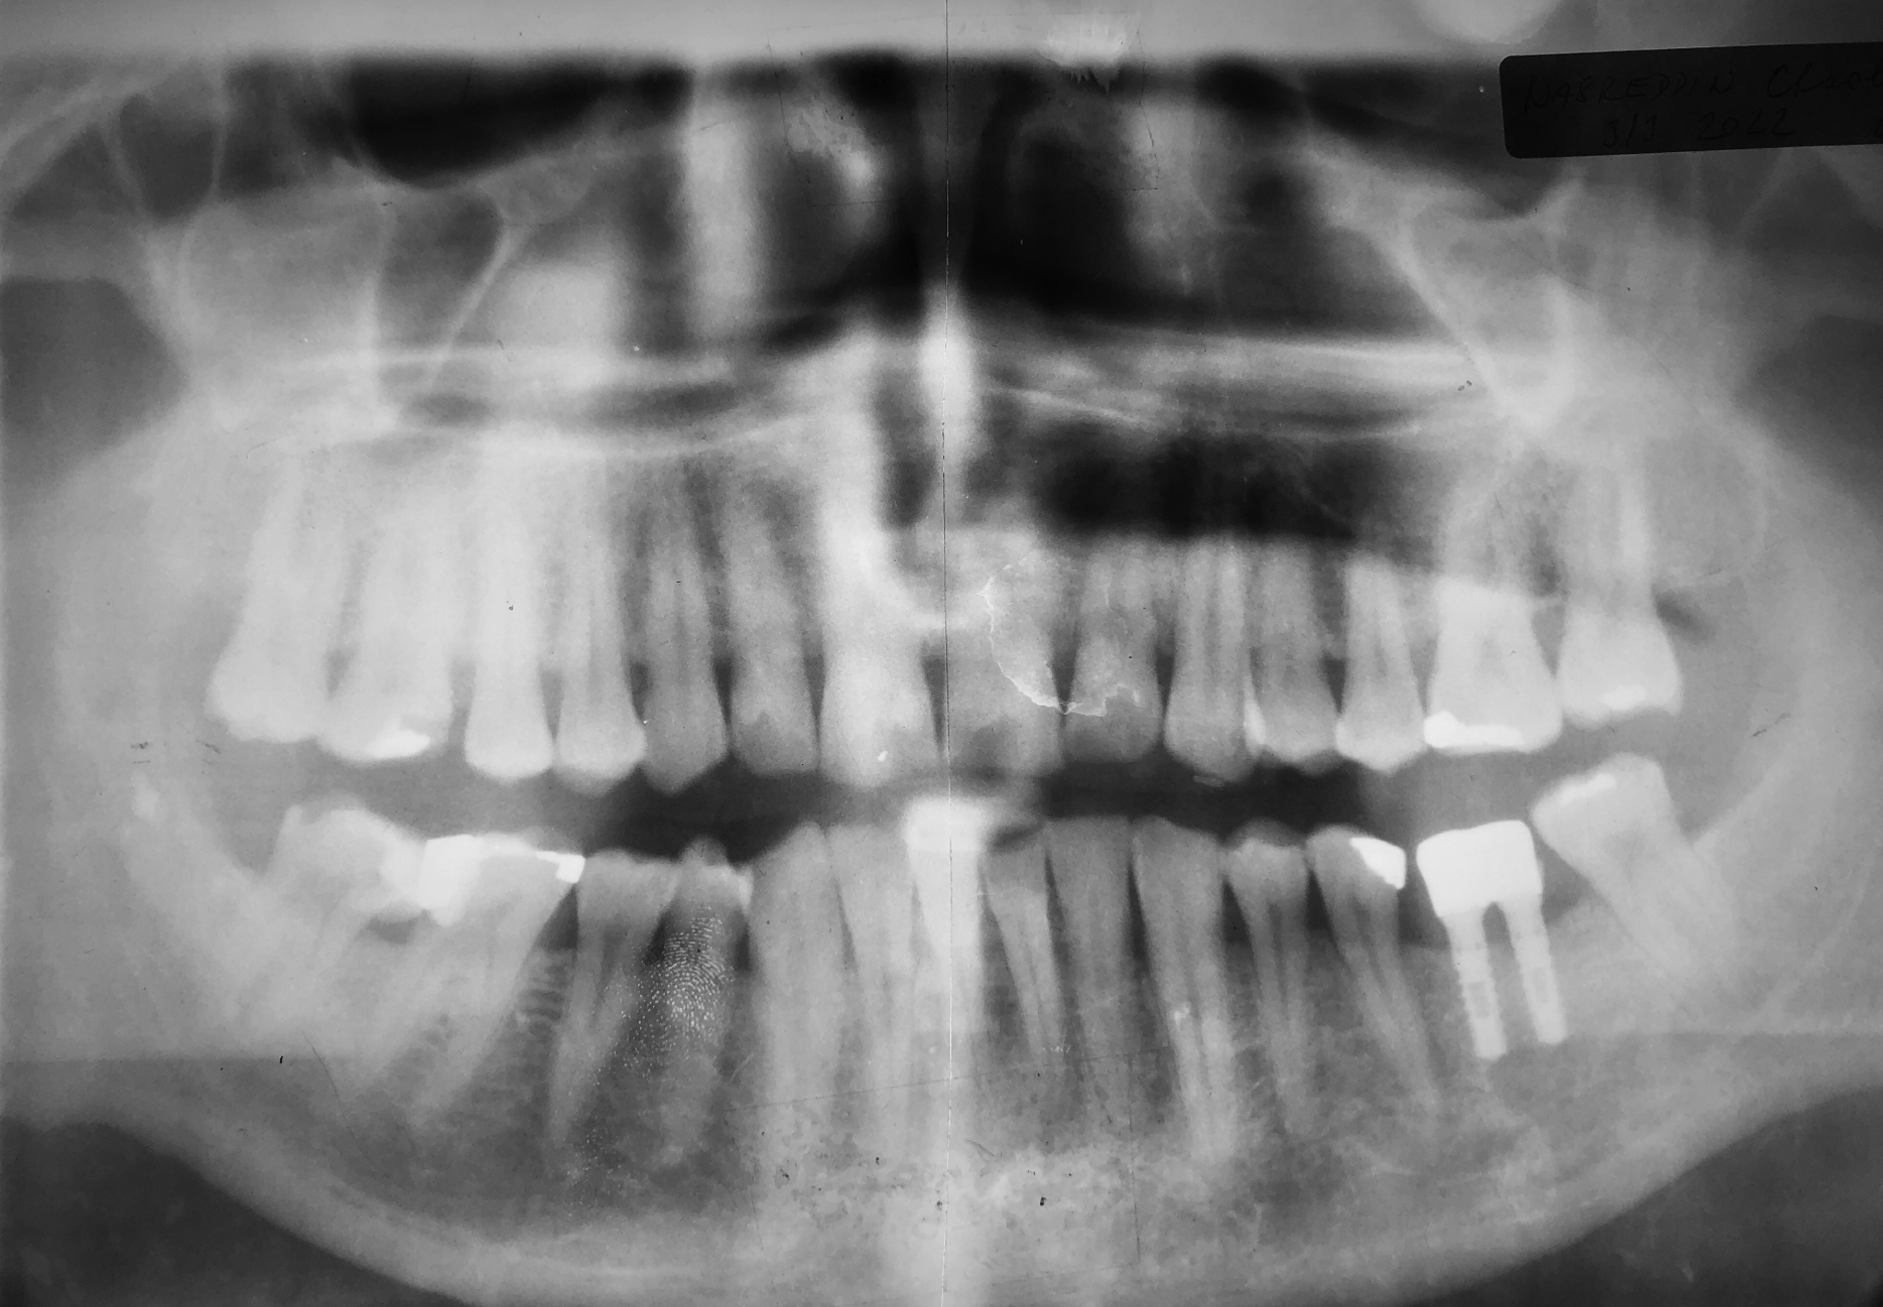

X-ray taken in June 2003 showing successful healing of the extraction site without the use of a bone substitute. Considering the width of the gap and the volume of the alveolar bone, two implants with a diameter of 2.9 mm were used.